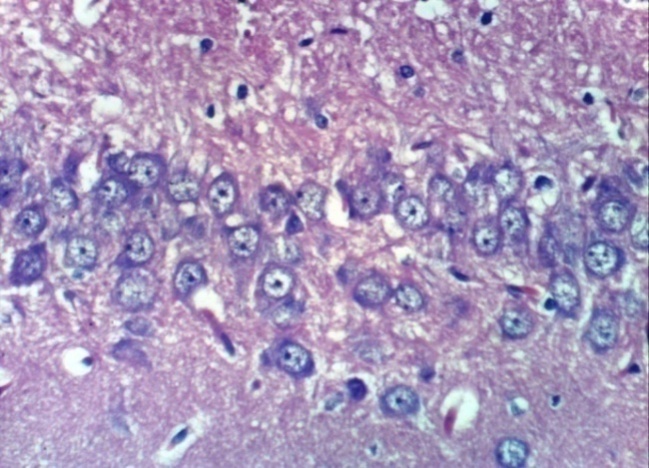

Microscopically, cerebral cortex of control, untreated rats revealed no histopathological changesas compared to normal control rats (Photomicrographs 1). Also, the cerabral cortex of treated rats with H. Pluvialis showed no histopathological changes(Photomicrographs 2,3) comparing to normal control rats. Meanwhile, cerebral cortex of rat treated with Al showed congestion of cerebral blood vessel (Photomicrograph 4), necrosis of neurons (Photomicrograph. 5) and multifocal cerebral haemorrhage (Photomicrograph 6). Examined sections from rats treated with rivastigmine revealed neuronophagia of sporadic necrotic neurons (Photomicrograph 7) and necrosis of some neurons (Photomicrographs 8). Some examined sections from rats treated with H. Pluvialis extract showed no histopathological changes (Photomicrograph 9), whereas, other sections revealed necrosis of neurons (Photomicrograph 10). In addition, the hippocampus of control, untreated rat revealed no histopathological changes (Photomicrographs 11 and 12). However, the hippocampus of rat treated with Al showed necrosis of pyramidal cells Photomicrograph. 13). Some examined sections from a rat treated with rivastigmine showed no histopathological changes (Photomicrograph14), whereas, other sections from this group revealed necrosis of some pyramidal cells (Photomicrograph 15).

Moreover, some examined sections from rats treated with H. Pluvialis extract showed necrosis of some pyramidal cells (Photomicrograph 16), whereas, other sections from this group revealed no histopathological changes (Photomicrograph 17). The lesion score in different experimental groups are demonstrated in the table (5), which declared a mild change in necrosis of neuron and pyramidal cells of hippocampus while the absence of cerebral haemorrhage and neuronophagia as a result of treatment of neurotoxic rats with either H. pluvialis or standard drug.

| Photomicrograph 13: Hippocampus of rat treated with AL showing necrosis of pyramidal cells (H and E X 400) | Photomicrograph 14: Hippocampus of rat treated with rivastigmine showing no histopathological changes (H and E X 400) |

Histopathological investigation of cerebellum and hippocampus of AD rats in the present results revealed necrosis of neurons and multifocal cerebral haemorrhage in addition to necrosis of pyramidal cells. While AD rats treated with neuronophagia of sporadic necrotic neurons and necrosis in the cerebellum as well as some necrotic pyramidal cells In accordance with the present results Salem et al. [1], showed severe congestion in the blood vessels with oedema in the meninges of AD-induced rats. While a micrograph of a brain section of AD-induced rats treated with rivastigmine showing no histopathological alteration in the hippocampus. These results are in agreement with the results of Bihaqia et al. [39], who showed the normal histological appearance of the brain cells treated with rivastigmine tartrate and revealed that rivastigmine reversed histopathological alterations caused by Al.

On the other hand, treatment of AD-induced rats with H. Pluvialis extract showed no histopathological changes in the cerebellum, whereas, other sections revealed necrosis of neurons. However no histopathological alteration was detected in the hippocampus of H. pluvialis extract treated AD rats, which may be contributed to, in AD induced rats ROS interact with nitric oxide (NO) to form peroxynitrite (ONOO−), a highly toxic compound. The bioavailability of endothelial NO is then reduced, and its vasoprotective effect is disrupted [40]. However, treatment with H. pluvialis containing antioxidant molecules, especially carotenoids, which play an important role in the control of the oxidative process. These antioxidant molecules (carotenoids) possess a strong antioxidant power due to their double-bonded structure, allowing the delocalization of impaired electrons, reducing oxidative damage and hence tissue architectures [2].